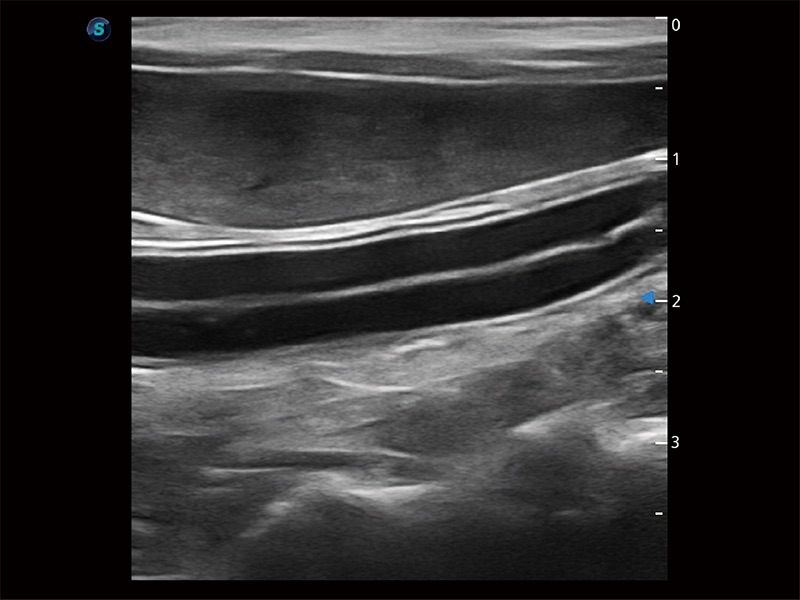

极大提升超低速微细血流的检出能力,同时更精准地滤除软组织和超声信号,为兽用医生提供以往无法通过常规血流获得的疾病诊断信息。

在传统二维血流成像的基础上,呈现血流的立体感,具有动感的生命力之美。即便是微小的血管也能轻松应对,提高了血流的视觉敏感性。

为精细结构及组织边缘提供高清晰度的图像和更大的成像视野。帮助减轻医生的用眼疲劳,快速精准获得测量的数据。